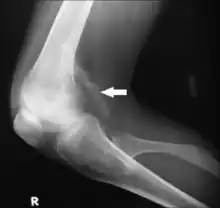

X-ray of right knee joint lateral view Ectopic Calcification seen extending posteriorly.

Typically, the diagnosis of extra-skeletal ectopic calcification is quite straightforward. A physical examination of a suspected area with calcified deposits palpates as hard and rough. To confirm, the calcified tissues can be seen on an x-ray.